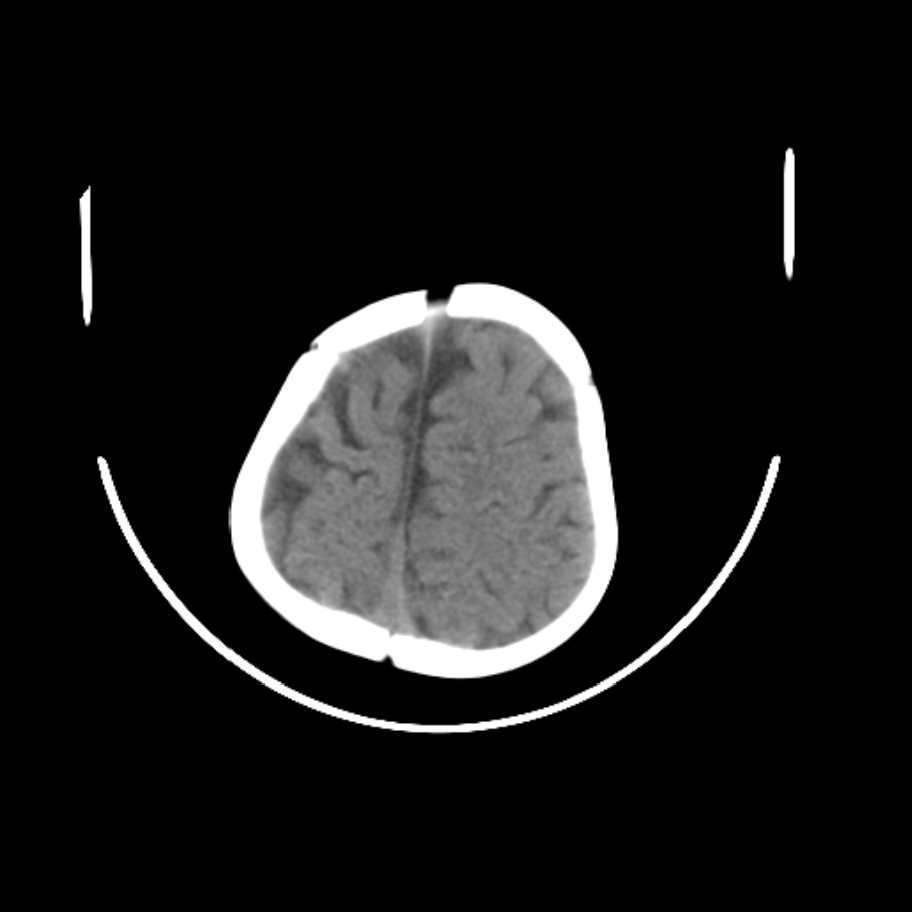

以下是引用随光逐影在2009-4-8 7:51:00的发言:[br]1)透明隔缺如(视-隔发育不良?)。2)右侧脑裂畸形。3)右侧幕上半球脑萎缩。